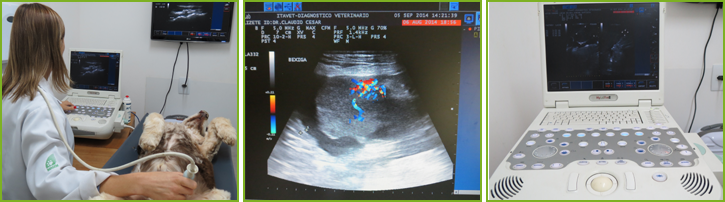

A ultrassonografia é um método de exame de imagem não invasivo, muito eficaz no diagnóstico de enfermidades abdominais, devido à sua sensibilidade aos tecidos moles, como órgãos internos, tecido subcutâneo, mamas e testículos. A ultrassonografia também é utilizada para acompanhamento gestacional e avaliação das regiões: cervical, torácica, articular e ocular. A ultrassonografia também é utilizada para guiar procedimentos como punções aspirativas e biópsias, dando agilidade ao diagnóstico final.

O Itavet dispõe de equipamento com Doppler colorido, que possibilita identificar e mapear a vascularização dos órgãos e tecidos, inclusive de tumores, e, Doppler espectral , que qualifica e quantifica esse fluxo vascular.

O aparelho de ultrassom não utiliza radiação ionizante. Produz suas imagens através da emissão de ondas sonoras pelos transdutores, que irão de encontro com as estruturas de interesse, retornando aos mesmos (eco), sendo transformadas em ondas mecânicas pelos cristais piezoelétricos, gerando a imagem de acordo com a densidade de cada tecido.